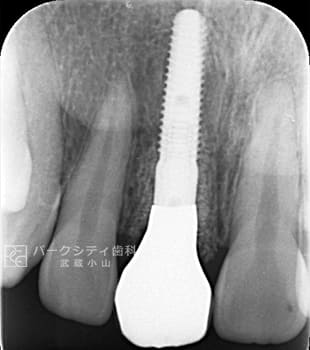

ルートメンブレンテクニックを併用した前歯部抜歯即時埋入の症例

ルートメンブレンテクニックとは歯根を一部温存することにより、顎堤の吸収を抑止することができるため審美的によい結果が得られます。また、今回大きな切開や移植などしていないため腫れや痛みも少なく、治療期間も短くてすみます。